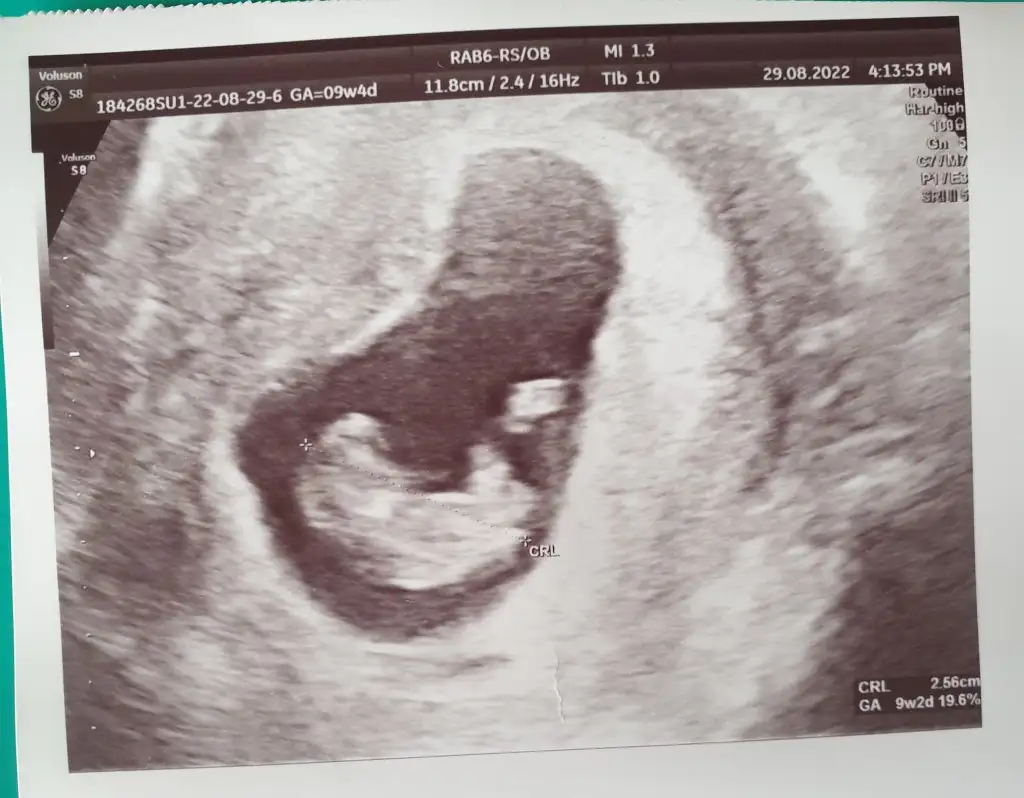

Pek anlamam ama içime erkek doğduKizlar iyi akşamlar

Cinsiyet tahmini yaparsaniz çok sevinirim, yoksa tahmin için çok mu erken bilemiyorum

Eki Görüntüle 3121368